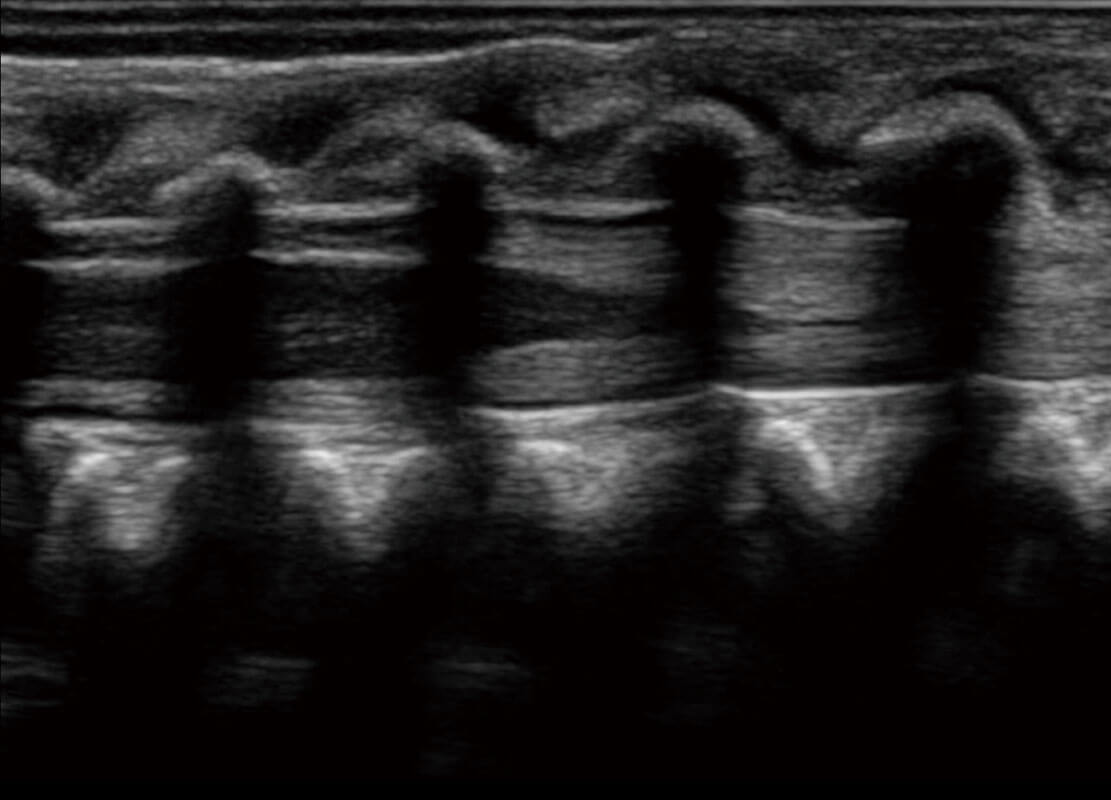

P60为盆底超声检查提供应用方案,多种腔内及腹部容积探头提供从二维、三维到四维的优异图像品质,实时快速三维容积数据获取,专业的测量工具包等人性化设计,为超声医生诊断提供有力保障。

能够简化盆底检查的操作流程,可在二维模式及三维成像模式下实现一键自动提取出标准切面、自动识别当前切面、自动测量,提升盆底检查的高效性,同时也能让青年医生快捷的获得准确的检查结果。